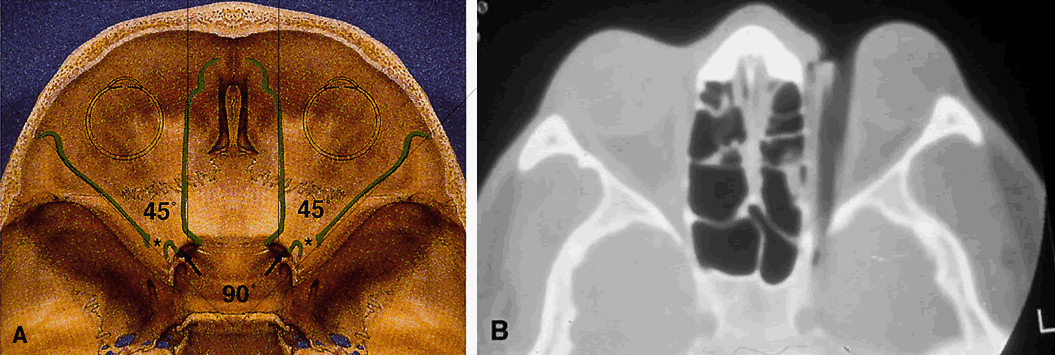

The lesser wing of the sphenoid bone is initially cartilaginous, but the greater wing and the rest of the orbital bones are membranous in nature and ossify and fuse between the 6th and 7th months of gestation. As the orbital bones develop, the eyes converge from an initial 180° relation to their final position of 68°, achieved in infancy. However, the orbital axis remains somewhat divergent at birth (115° between the lateral orbital wall and the skull axis) when compared with that of adults (45°) (Fig. 4).15

Fig. 4. Angular separation of the globes at 2 months' gestation, 3 months' gestation, birth, and adulthood. (Fries PD, Katowitz JA: Congenital craniofacial anomalies of ophthalmic importance. Surv Ophthalmol 35:87, 1990)

The SOF is 22 mm long and separates the greater and lesser wings of the sphenoid bone. Note in Figure 8 that it lies lateral and slightly below the optic foramen in radiographic studies. Also note that the (SOF, and not the optic foramen, is located at the apex of the orbit (Fig. 11). The SOF is split into two compartments by the lateral rectus muscle. The medial compartment contains the oculomotor (superior and inferior divisions) nerve, nasociliary nerve, abducens nerve, sympathetic and parasympathetic fibers, and superior ophthalmic vein. The lateral compartment transmits the lacrimal, frontal, and trochlear nerves. This extraconal location of the trochlear nerve is appreciated clinically after retrobulbar anesthesia. Although the anesthetic block effectively causes akinesia of the EOMs, the patient often can still intort the globe because of the intact innervation to the superior oblique muscle.

Fig. 11. Osteology. A. An axial view of the orbital roof demonstrates the parallel course of the medial orbital walls (green). The lateral orbital walls (green) lie at an angle of 90° from each other, or 45° from each medial wall. Remember that the superior orbital fissure, and not the medially placed optic canal, lies at the posterior aspect of the orbit. B. CT of a wooden foreign body within the orbit after trauma. Note that the tip has traveled through the superior orbital fissure and lies within the CS, not the optic canal. In this case, the greatest worry was not the patient's vision, but the possibility of lacerating injury of the carotid siphon, which was confirmed on subsequent arteriography (A modified from Zide BM, Jelks GW: Surgical Anatomy of the Orbit, p 9. New York, Raven Press, 1985. B courtesy John W. Shore, MD, Austin, TX)